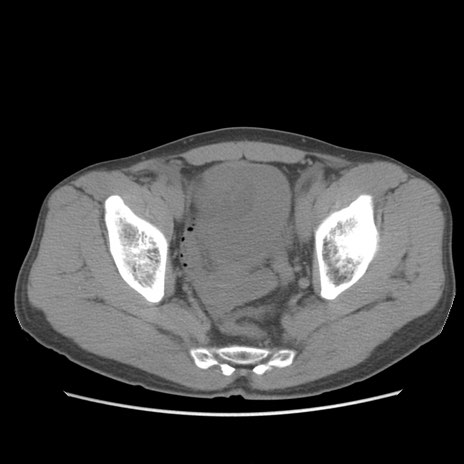

症例56 CT(横断像)

脂肪ウインドウ